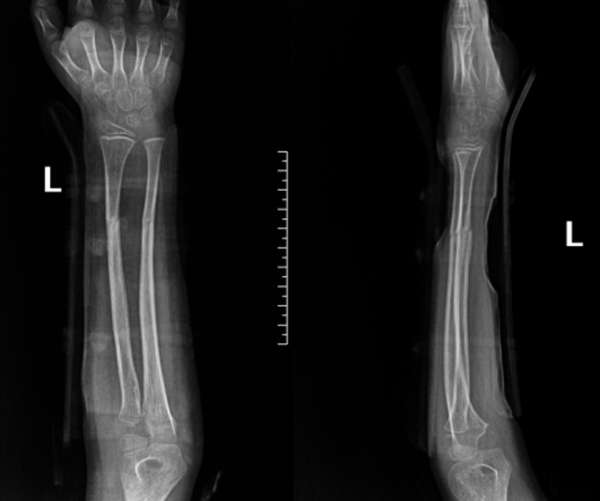

复位后,医护团队为家属详细指导护理事项,并制定系统复查计划。在随后数周的跟踪随访中,患儿骨折位置维持稳定,未出现移位。直至拆除夹板之日,其左前臂功能已基本恢复,骨骼愈合近乎完美。

伤后15天复查

伤后25天复查

伤后34天复查

伤后48天复查

伤后58天复查